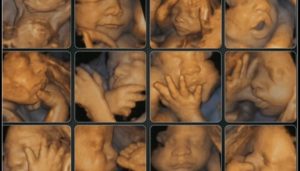

- благодаря объёмным изображениям можно более детально рассмотреть некоторые мельчайшие структуры, которые тяжелей исследовать при обычном двумерном режиме;

- разобраться в изображении, полученном при 4Д УЗИ, намного легче;

- при проведении четырёхмерного ультразвукового исследования особенную ценность для диагностики внешних пороков развития представляет дополнительная информация: вы развеете все сомнения, когда сами пересчитаете все пальчики на маленьких ножках и ручках, убедитесь в отсутствии других внешних пороков развития. Кстати, именно подозрение на наличие любых отклонений и может стать показанием для проведения 4D УЗИ;

- благодаря 4D УЗИ врач сможет оценить сам плод в целом и различные части его тела одновременно в трёх проекциях, что немаловажно для выявления аномалий во внутриутробном развитии;

- благодаря данным такого четырехмерного исследования вы получите дополнительную информацию, необходимую при диагностике пороков развития: лица, конечностей и позвоночного столба. При таком УЗИ более отчётливо можно увидеть пол малыша;

- вы сможете оценить мимику малыша, благодаря чему вы увидите, какие эмоции он испытывает — радость, огорчение или апатию. Вы легко сможете понять его чувства. Не является секретом тот факт, что правильно развиваться плоду помогают хорошие эмоции, но плохие эмоции помогут задуматься о серьёзных проблемах, испытываемых ребёнком. Например, подавленное апатичное состояние плода может сигнализировать об асфиксии — недостаточном поступлении кислорода, из-за чего возможен целый ряд проблем. Искажённое от боли личико малыша может «рассказать» о неправильном развитии внутренних органов, что вызывает у него боль;